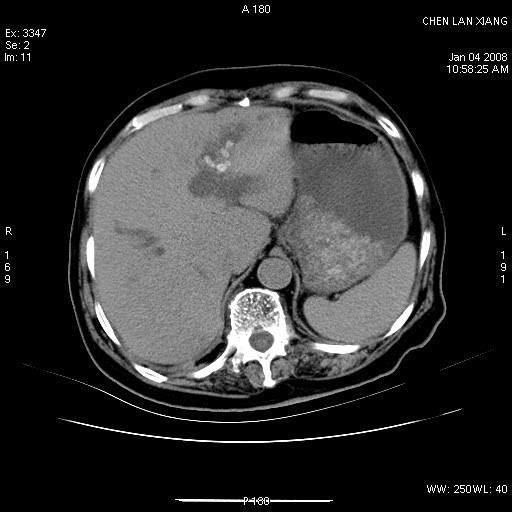

女,76岁,腹痛3-4天,b超示:肝内实性肿物,胆囊强回声,胆总管扩张.

考虑:1、胆总管下端结石伴梗阻性肝内外胆管扩张(肝左叶外侧段肝内胆管多发结石、胆管炎);

2、肿囊癌累及肝,不除外 黄色肉芽肿性胆囊炎。

1 胆总管末端结石伴肝内胆管结石,肝内外胆管扩张。2 胆囊扩大,胆囊壁不规则增厚,内见软组织密度影。考虑:慢性胆囊炎,不除外胆囊癌!

ct所见:1、 肝内胆管结石,肝内外胆管扩张。低位胆道梗阻,胆总管下端结石;2 胆囊扩大,胆囊壁不规则增厚

考虑:胆总管下端结石并肝内外胆管扩张,肝内胆管结石;

慢性胆囊炎

标题: 肝右叶病灶

胆囊癌侵犯肝右叶?

1)胆囊癌伴肝脏转移。2)胆总管下端结石、肝内胆管结石伴肝内外胆管扩张。